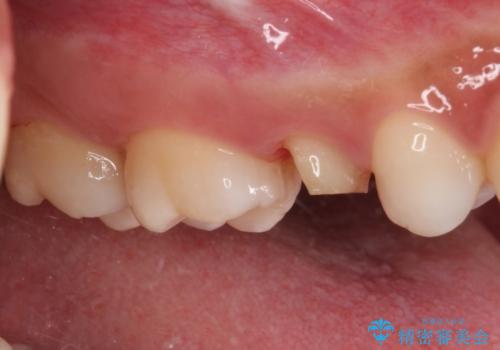

- 根管治療が必要な虫歯を放置した結果、抜歯が必要と診断されたとのことで来院された患者様です。

口腔内の状態やレントゲン写真から判断し、長期的なことを考えると抜歯が無難と思われましたが、それを承知の上で保存するための処置を行うこととしました。

まずは虫歯を除去した上で根管治療を行い、部分矯正により骨内深い位置にまで及んだ健全な部分を引っ張り出すこととしました。